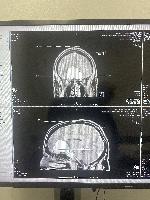

MRI, front and side views